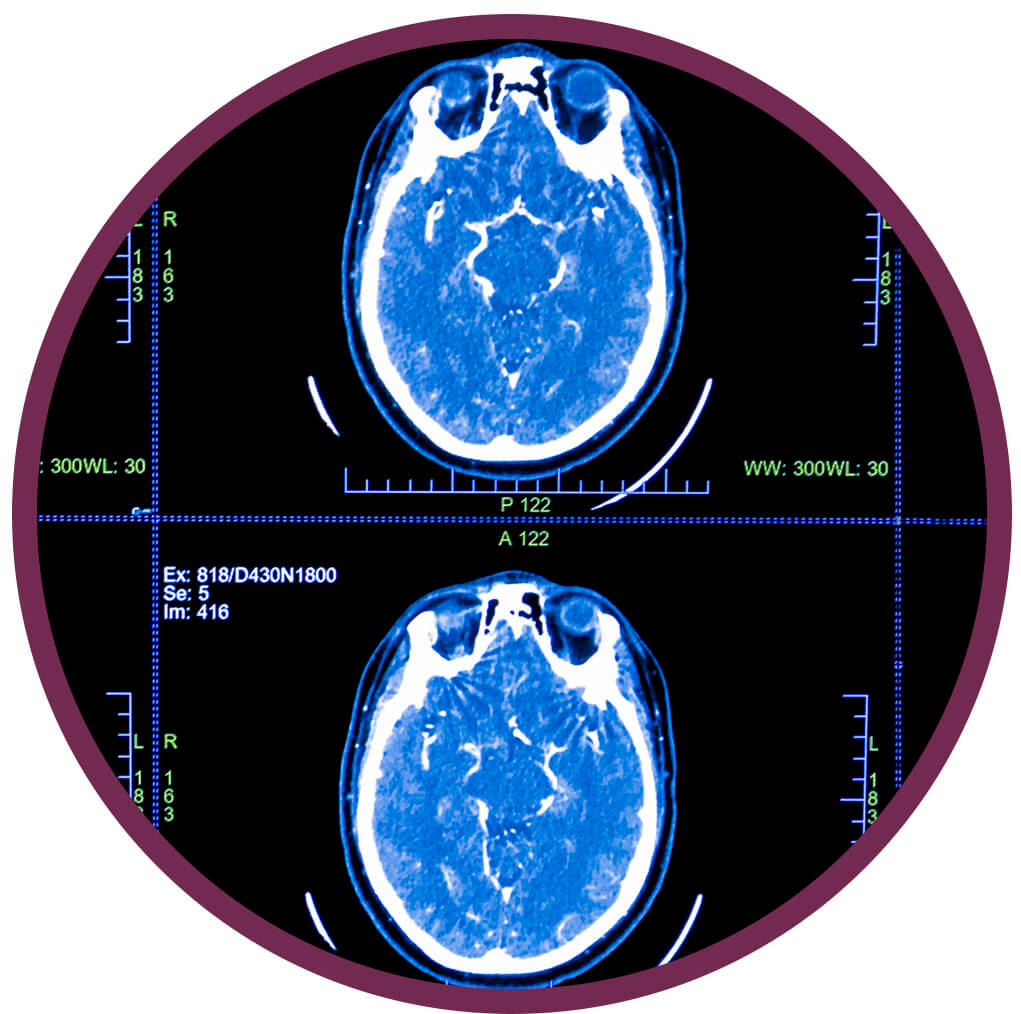

Agykoponya CT

AGYKOPONYA NATÍV ÉS KONTRASZTOS CT ÉS AGYI ANGIOGRÁFIA

Milyen tünetekkel forduljunk hozzánk?

Az agyi és idegrendszert érintő kórképek esetén rendkívül változatos panaszok jelentkezhetnek, az idegrendszer károsodása ugyanis más betegség szövődményeként is kialakulhat. Az alábbi tünetek jelentkezése esetén keressen fel ideggyógyász szakorvost:

- hosszú ideje fennálló, rendkívül erős, vagy gyakran jelentkező fokozódó fejfájás

- szédülés

- egyensúly- és mozgáskoordinációs zavar

- féloldali végtagzsibbadás

- féloldali végtag gyengeség

- beszédzavar

- látászavar

- vegetatív zavarok (remegés, szívdobogás érzés, emésztőrendszeri panaszok)

- epilepsziás görcsök

- eszméletvesztés

- a gondolkodás zavara

- memória zavarok

Tudnivalók:

Az agykoponya CT vizsgálat előtt fontos a családorvossal. kezelőorvossal, ideggyógyásszal, belgyógyásszal vagy onkológussal történő konzultáció, hisz a CT vizsgálat során, sugárterhelés és kontrasztanyag adása is történik, így a vizsgálatot csak orvosi javaslat alapján végezzük. A vizsgálat előtt 6 órával már nem szabad enni, tiszta vizet azonban a beteg fogyaszthat. A kontrasztanyag adása előtt meg kell vizsgálni a vese működését jelző labor paramétereket, mivel súlyosan károsodott (beszűkült) vesefunkció illetve pajzsmirigy betegség esetén a kontrasztanyag adása lehetőség szerint elkerülendő. Ismert kontrasztanyag allergia esetén a kontrasztanyag adása tilos (kontraindikált).

Hogyan végezzük a vizsgálatot?

A CT-készülékünk egy nagy, vastag gyűrűhöz hasonlít, melynek aljában egy asztal van, ami mozog. Ön ezen az asztalon fekszik mozdulatlanul, miközben a felvételeket készítünk. Szükség esetén intravénás kontrasztanyagot adunk, melynek mellékhatásáról tájékoztatást kap. A vizsgálószerkezet működése közben zúgó, búgó hangot ad ki, de ettől nem kell megijedni, hisz a vizsgálat fájdalommentes. A vizsgálat közben Ön folyamatosan audiovizuális kapcsolatban van az operátorral.

Mikor nem végezhető el a vizsgálat?

A CT vizsgálat röntgensugarakkal történik, ezért terhesség alatt nem ajánlott.